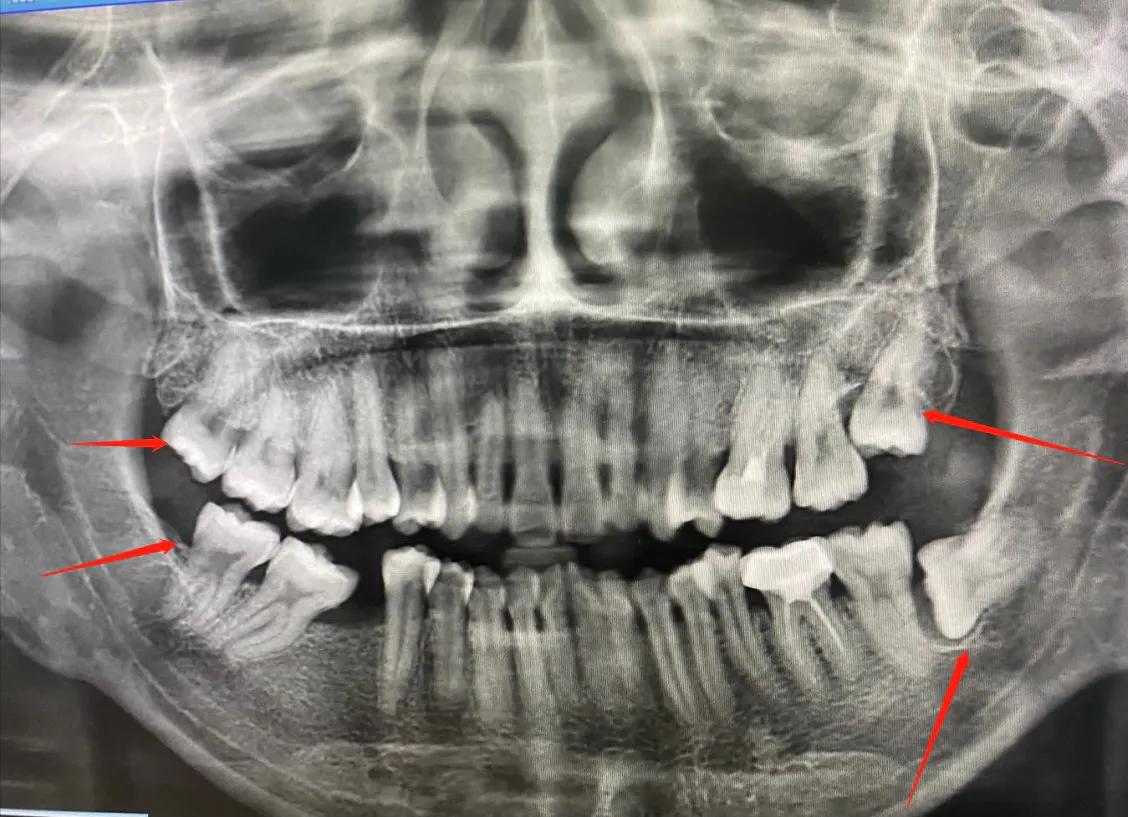

我在2020年下半年我补过的蛀牙因为上火隐隐作痛,然后我去了深圳市宝安人民医院做了检查拍了一次牙片,医生看了我牙片说左上颚蛀牙治疗不彻底,现在依然在发炎,右边下颚拔大牙后没有补上,缺牙过久导致受力不均,旁边的牙齿前倾牙列变形,可以通过矫正把牙齿排放整齐减少牙周病,隐形牙套矫正五万,钢牙不适用与我。

我从网上各个方面收集了资料、询问了牙科朋友,一个博士牙科医生说可以通过矫正解决,另外一个经验丰富的牙科医生说当务之急先去治蛀牙,然后我挂了罗湖人民医院根管治疗医生说如果要矫正应该先看矫正医生,牙齿就像房子的构造、矫正牙齿做出方案后再进行矫正治疗。我听了很有逻辑很在理,深圳牙科火爆哪里都挂不到号,偶然挂到龙华人民医院的矫正医生,他由于我口腔问题多蛀牙根管治疗建议我找市级医院治疗说我要移动牙齿填补空隙比较难实现建议我去市级大医院。于是我就近原则去了我住的地方附近坂田医院,一个微胖的牙科医生看见我分外热情跨越过各种各样的病人叫护士插队给我拍牙片,建议我治疗蛀牙,缺牙通过剜掉旁边临近两颗牙种牙拔智齿,想立马给我躺下开始做。我偶然发现同层同事箍牙我问她在哪里做的,她说在同步牙科连锁店还把医生推荐给我,我咨询了一下,他们给的方案是里面拔牙种牙,相对大医院的矫正方法,诊所的方案倾向于能种牙的不移牙,智齿能拔牙的没有考虑要不要拔没有说智齿可变成备用牙,另外还有另外一家不知名诊所想立马给拔牙缴费。经历了高中时期的拔大牙没有种导致牙变形和后来蛀牙根管治疗彻底后,我已经意识到我要找正规专业的大医院的重要性。